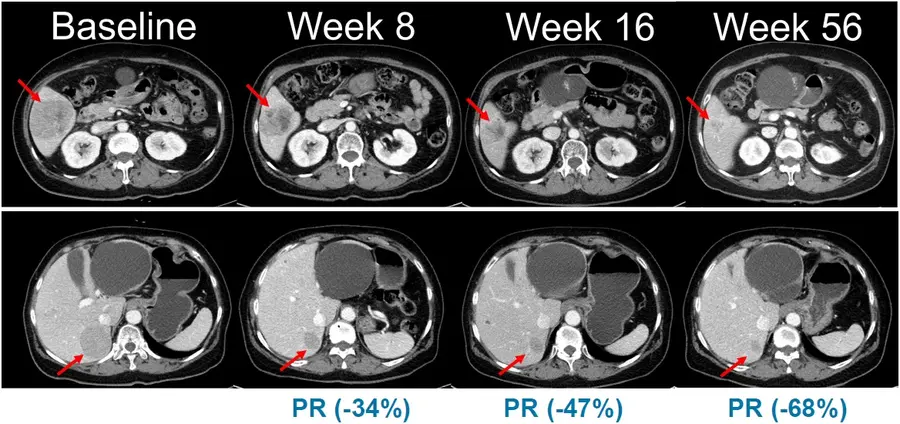

이번 임상 2상은 총 45명의 환자를 대상으로 표적 항암신약 벨바라페닙과 MEK 억제제인 코비메티닙(Cobimetinib) 병용요법의 유효성과 안전성을 평가하기 위한 다기관, 단일군 시험으로 진행된다.

특히 NRAS 돌연변이 흑색종은 예후가 불량하고 국내외 허가된 표준 치료제가 없는 의료적 미충족 수요가 높은 영역으로, 현재 의료 현장에서는 벨바라페닙이 치료목적사용 승인을 통해 일부 환자에게 제한적으로 투약되고 있다.